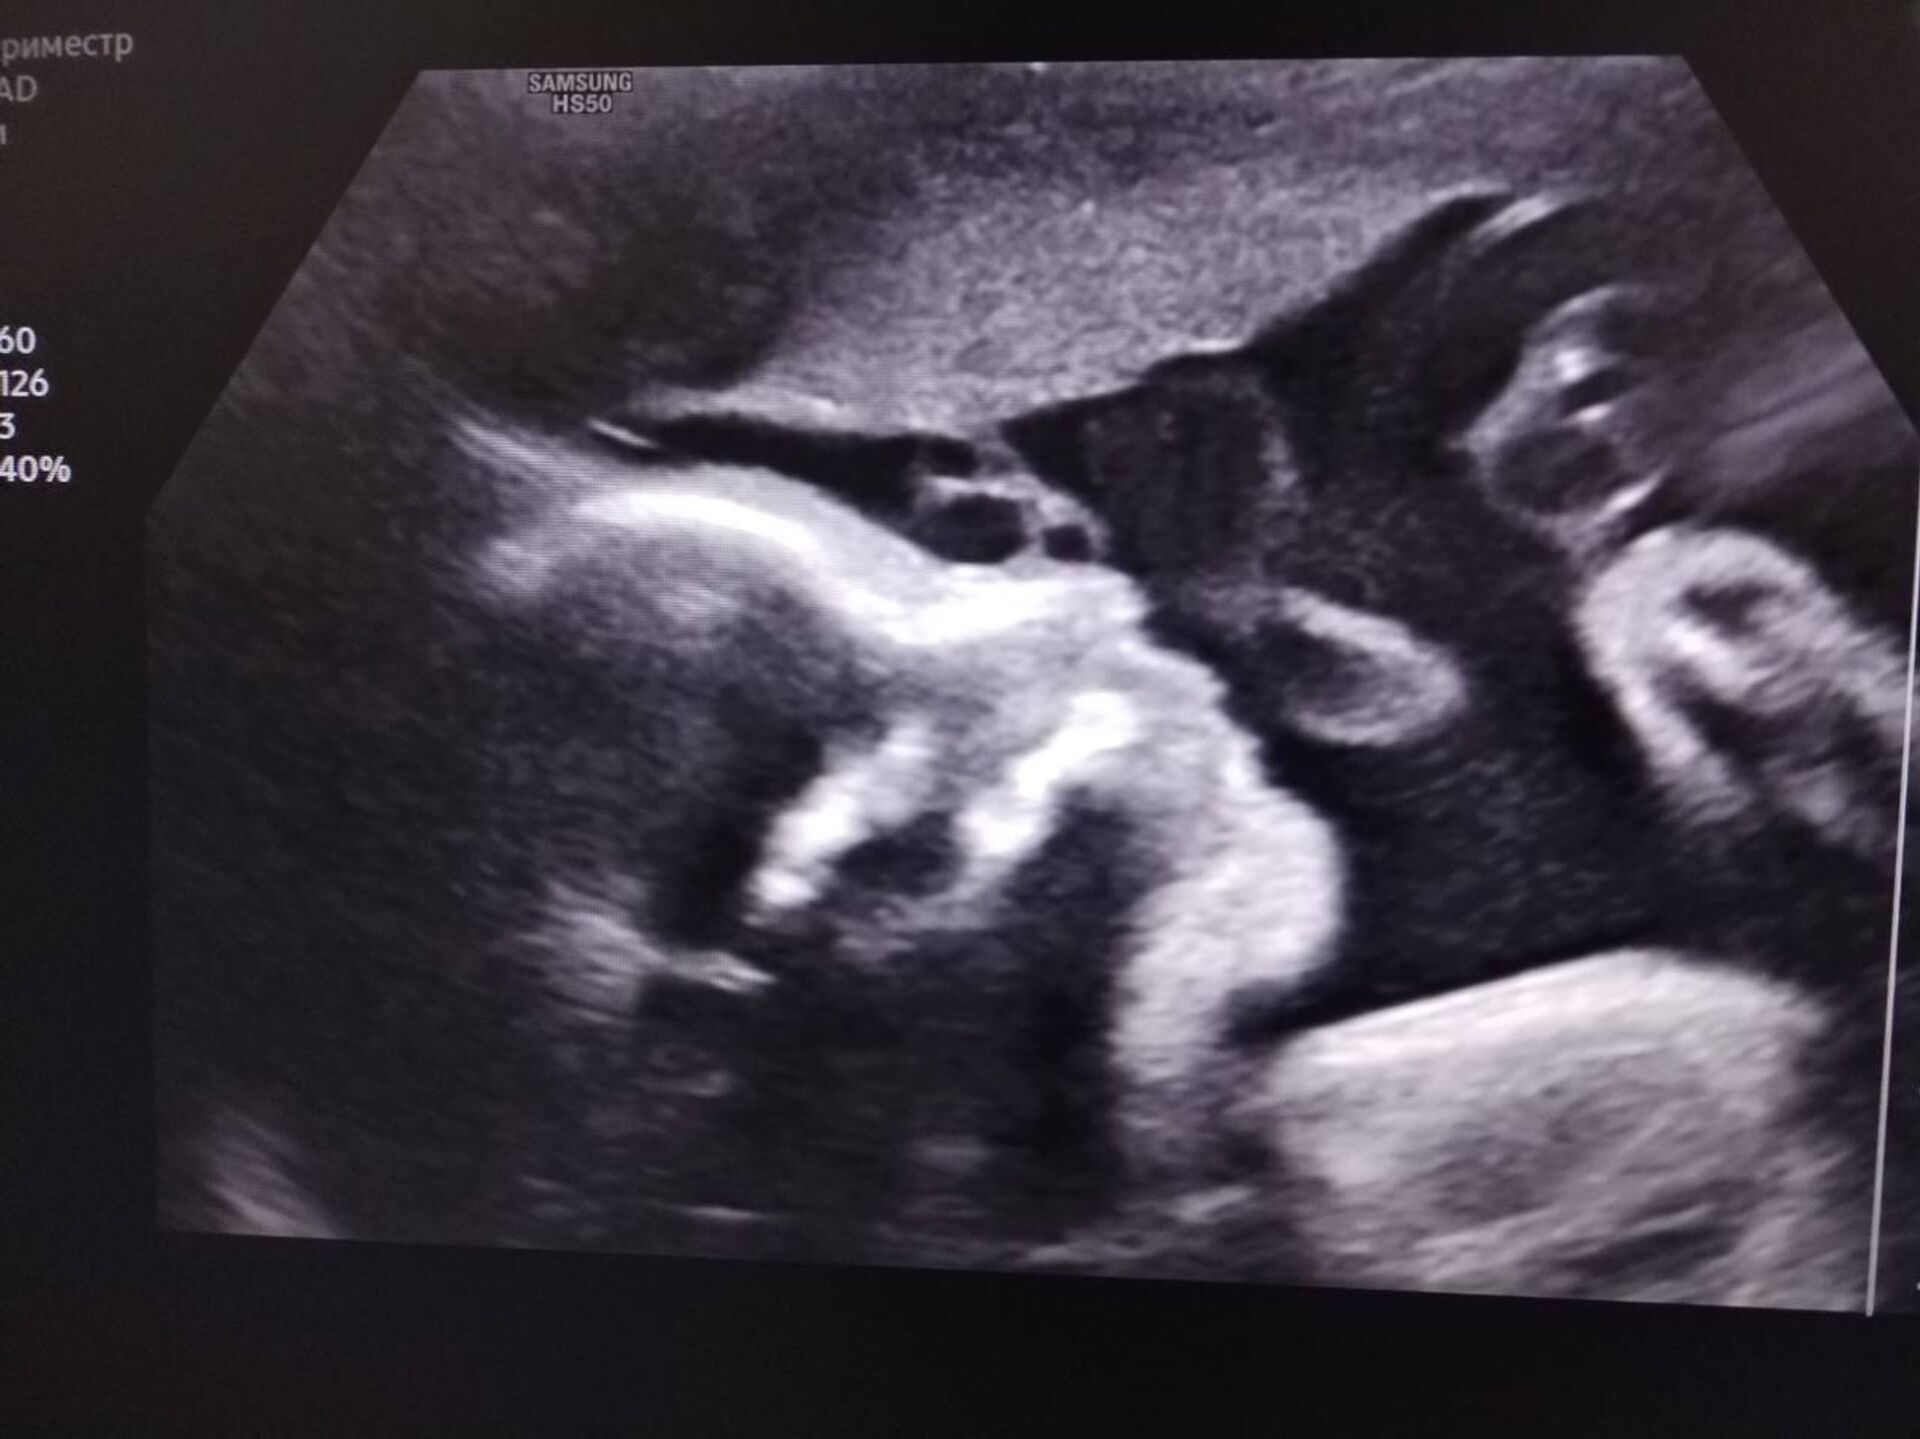

Чудо под сердцем

© Photo : Из семейного архива Кристины и Евгения